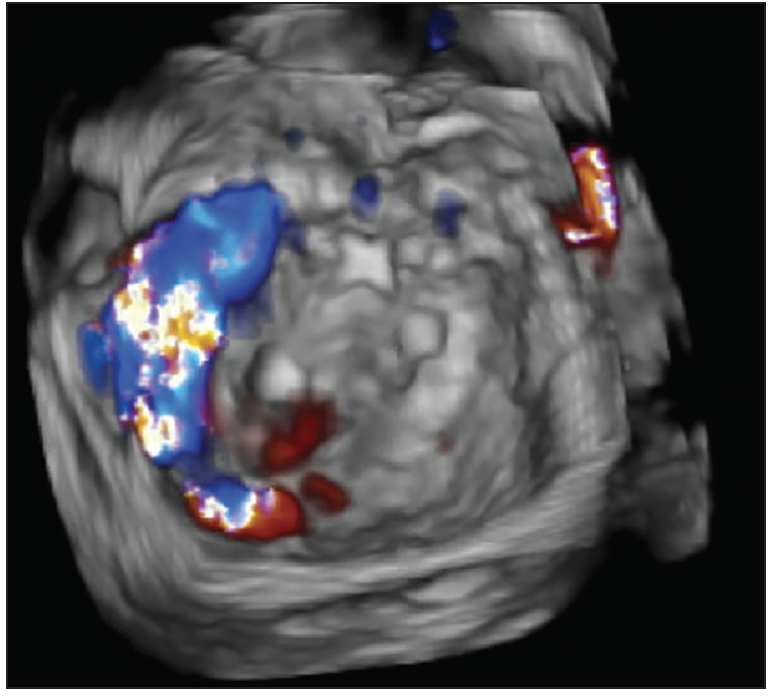

The most important imaging modalities for diagnosis and to guide treatment are gated-heart CT and transesophageal echocardiography (TEE), particularly when paired with three-dimensional (3D) reconstruction (ie, 3D TEE). CT affords the advantage of determining the precise location of the PVL, as well as the advantages of image reconstruction and calculation of optimal imaging angles for the catheterization lab when transcatheter PVL closure is anticipated (Figure 1). CT also allows for understanding of the size and course of the PVL with a high degree of spatial resolution, as PVLs may be serpiginous and complex. TEE and 3D TEE are important in quantifying PVL severity and identifying the PVL location and are critical for in-lab procedural guidance—particularly for mitral PVL closure (Figure 2). Three-dimensional printing has been described to guide optimal device selection.17 However, it is unknown whether 3D printing enhances the procedural efficiency and/or clinical outcomes of PVL closure, and the attendant overhead costs may be considerable.

For procedures in which antegrade wiring is chosen, the transseptal puncture can be performed per institutional practice with standard equipment. Electrocautery may be required if a previous interatrial septal repair has been performed or scar tissue is present. The transseptal puncture location is typically posterior and inferior in the fossa ovalis, which affords the most backup support when traversing the PVL with a catheter. Antegrade wiring is performed with a 0.035-inch stiff angled hydrophilic wire, facilitated by use of a steerable transseptal sheath (eg, an 8.5-F Agilis sheath, Abbott Vascular) with a telescoping 5-F multipurpose diagnostic catheter and 6-F multipurpose guiding system within it. This entire telescoping system can be manipulated in three dimensions to approach the PVL. Wiring of the defects is performed using both fluoroscopic guidance and TEE. Three-dimensional TEE is critical during this process to guide the operator steering the system, as well as to confirm the wire position across the defect rather than through the valve (Figure 6A). Once the PVL is crossed, the wire can be exchanged for a stiff ventricular wire (using a telescoping system as previously described) or used to create a transcatheter “wire rail,” which produces optimal backup support. A transcatheter wire rail is created by directing the hydrophilic wire into the ascending aorta, which is then snared and externalized via femoral artery access, thus providing maximum support for catheter or sheath crossing (Figure 6B and 6C).

Figure 6. Three-dimensional TEE guiding a mitral PVL procedure for an anterolateral defect at the 10 o’clock position along the mitral annulus (A). The catheter and wire are shown crossing in the interatrial septum and approaching the defect. Panel B shows the formation of a transcatheter wire rail. A steerable guide catheter was used to guide a hydrophilic guidewire across the PVL into the left ventricle, which was then directed through the aortic valve and snared in the ascending aorta. A transcatheter wire rail is seen after the hydrophilic wire was snared in the ascending aorta and externalized via femoral artery access (C). Over the wire, a catheter was advanced across the PVL into the left ventricle, and the first AVP II was deployed across the defect. The wire was maintained in place after the device was deployed to allow access to the PVL for further devices. Panel D shows the final image of the mitral PVL case with three AVP IIs deployed.